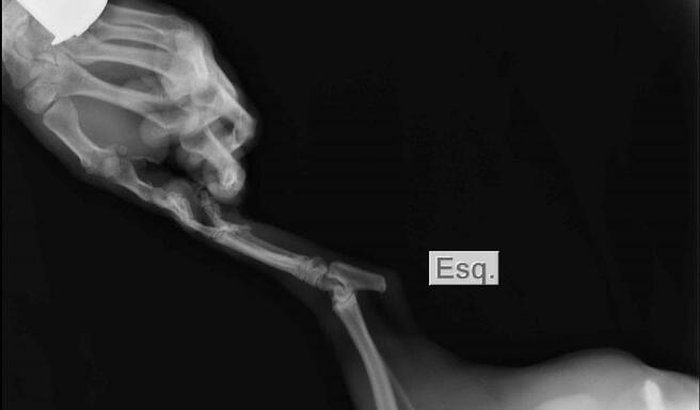

Operação de perna Orion

Sou marian e criei essa vaquinha pra recaudar 2.800,00$ para fazer a operação de meu cachorrinho que foi atropelado na frente de minha casa o dia de hoje 22/02/2023,  ver tudo

Sou marian e criei essa vaquinha pra recaudar 2.800,00$ para fazer a operação de meu cachorrinho que foi atropelado na frente de minha casa o dia de hoje 22/02/2023,